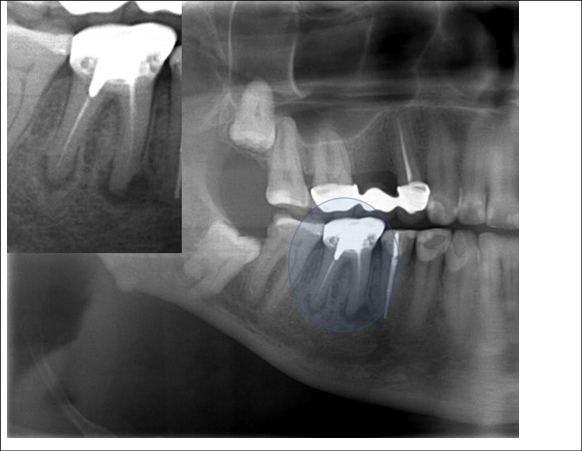

Figure 5 Periapical radiography of the molars and lower premolars region D. The dotted oval areas identify endodontic treatments for tooth roots 46. There is a prosthetic fused metal core to support the metallic crown on that same tooth. See that the root fillings are below the apical limit, and this characterizes iatrogeny. There is an apical radiolucent image, which may mean repair.

Figure 6 Panoramic radiographic technique performed with the Frankfurt Plan slightly higher than the standard position, to "open" the interproximal spaces in the posterior teeth, making the smile line straighter .

Figure 7 Panoramic X-ray cutout showing highlighted tooth 36, mesiangulated, with a coarse excess on its distal face, that causes iatrogeny, even though it has free access due to the absence of tooth 37. This tooth was treated endodontically, at first, in a correct way.

Figure 8 Panoramic X-ray cutout showing highlighted teeth 36 and 38, with a coarse excess on its distal face of tooth 36. In fact, there is an entire contact face, instead of a contact point, too, due to mesiangulation of tooth 38 that causes iatrogeny .